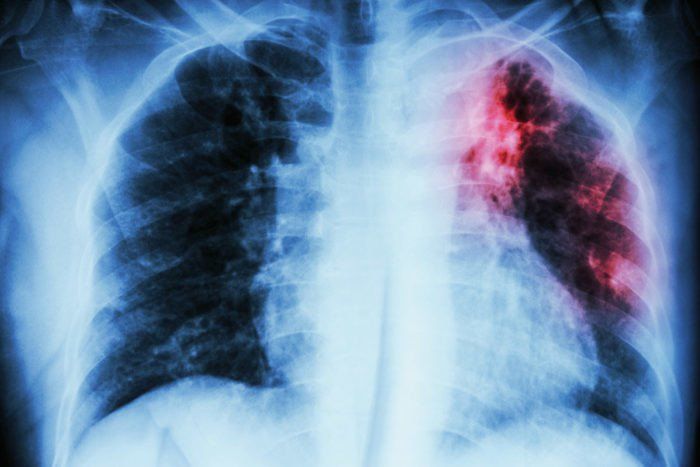

Những tổn thương cơ bản ở bệnh phổi phát hiện trên X quang

1. Những tổn thương cơ bản ở bệnh phổi phát hiện trên X quang

Chụp X quang là kỹ thuật chụp được sử dụng nhiều nhất trong y khoa, giúp bác sỹ có thể đánh giá, phát hiện những triệu chứng bất thường của phim chụp X quang phổi, từ đó có thể giúp các bác sỹ lâm sàng đưa ra chẩn đoán sơ bộ. Bài viết sẽ cung cấp thông tin về những tổn thương cơ bản của phổi phát hiện trên X quang.

Căn cứ vào mức độ cản tia X của tổn thương, các tổn thương ở phổi được chia làm ba dạng là hình mờ, hình sáng và hình mờ - sáng kết hợp.

- Lao phổi: Đám mờ không thuần nhất, ranh giới không rõ. Tổn thương ở nhiều giai đoạn phát triển khác nhau: thâm nhiễm, xơ, vôi hóa,..